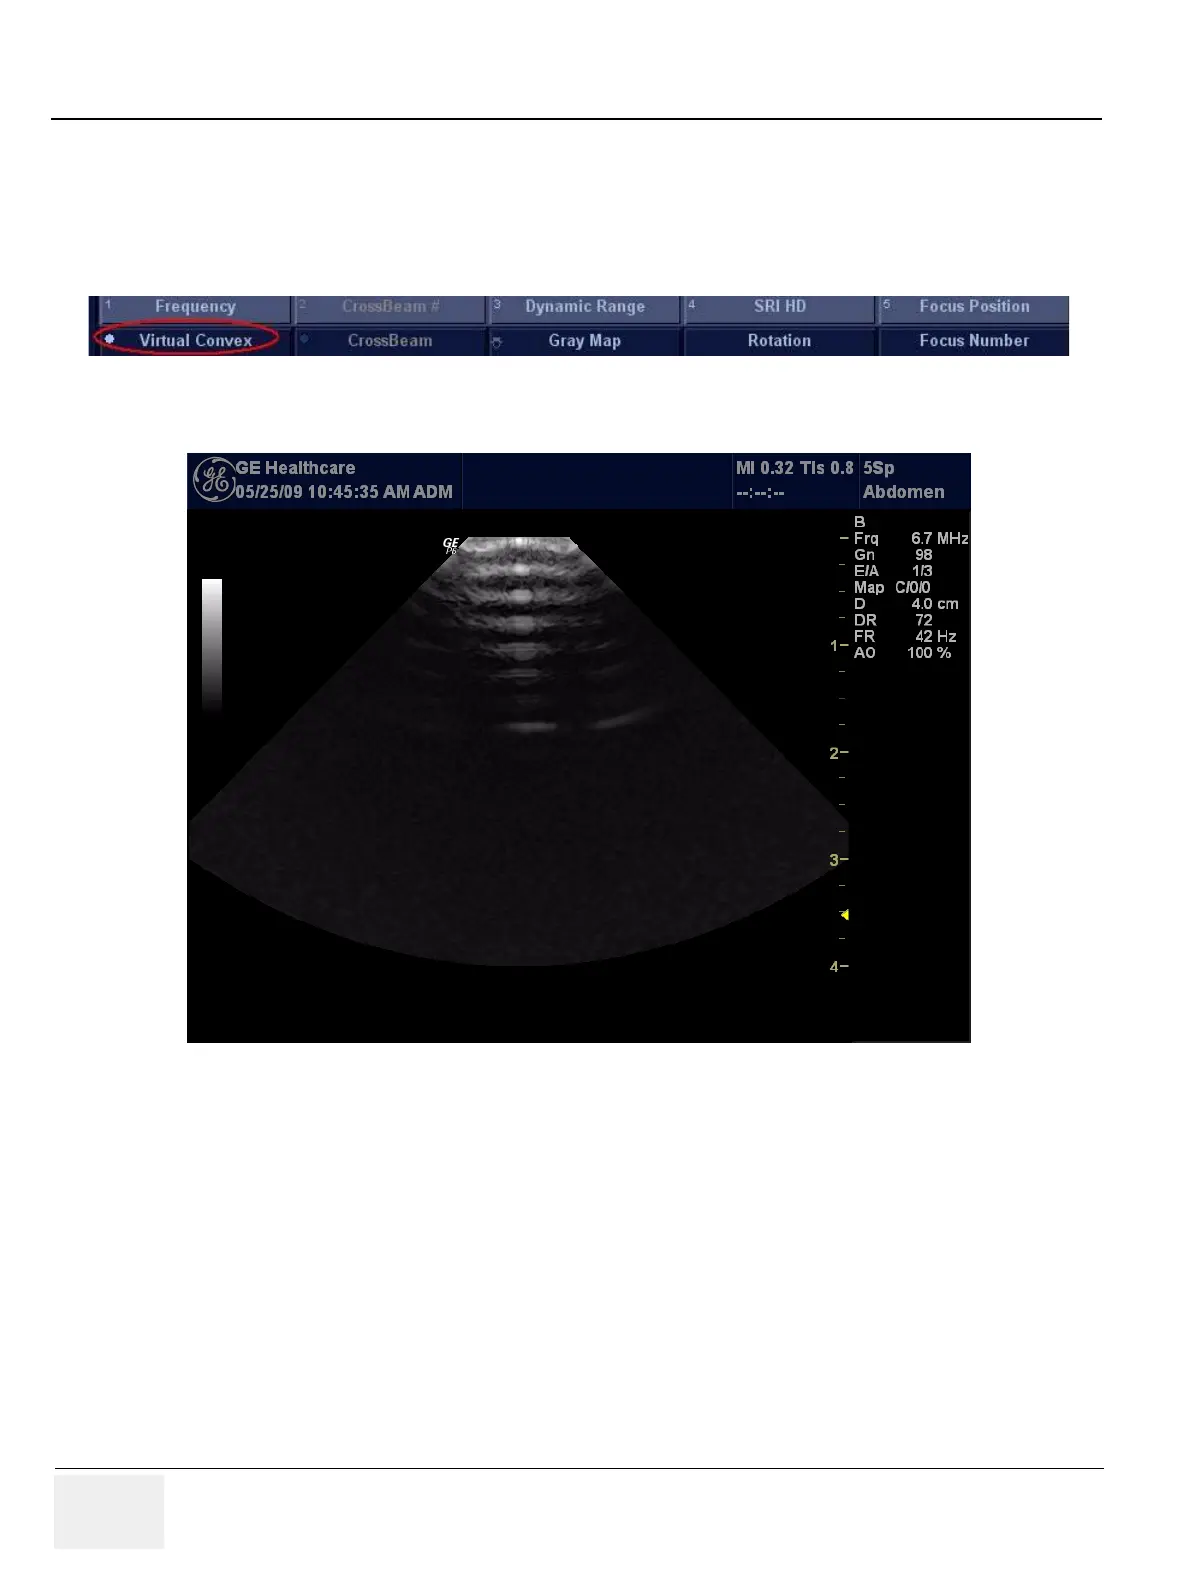

4-9-4 CWD64 Assy Function Validation Procedure

1.) Insert the Sector probe in probe port.

2.) Turn on the system.

3.) Press Virtual Convex button to enable Virtual Convex if not already enabled.

Figure 4-39 Virtual Convex Enabled

Figure 4-40 Virtual Convex